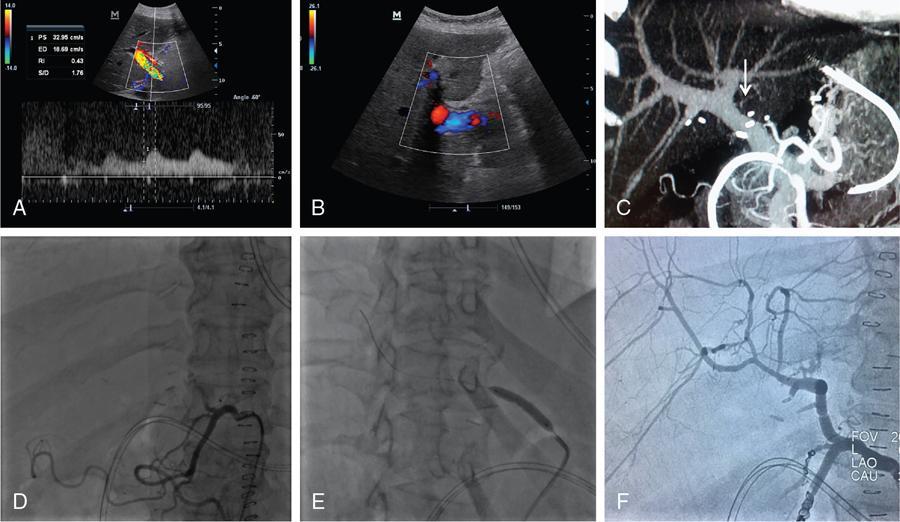

M.C. Uthappa, Soumil Singhal Liver transplantation is performed in patients with end-stage liver disease or patients with acute liver failure. The world’s first liver transplantation was performed by Dr. Thomas Starzl in 1963. Thousands of transplant surgeries are being performed in India every year. Each transplant reflects an outstanding benevolence of the donor and the family. However, India still ranks quite low in the organ donation program, because of which several patients are waiting on the transplant list eagerly. Transplantation surgery is a multidisciplinary approach involving surgeons, physicians, anaesthetists and nursing teams who work through the complexity to achieve a good result in every patient. The evolution in the operational technique and intensive care units have helped reduce both morbidity and mortality rates, resulting in improved survival outcomes. Orthotopic transplantation is the commonly performed technique that is performed on the adult and paediatric populations worldwide. Despite advancements in transplantation surgery, complications are inevitable in some clinical scenarios. Both diagnostic and intervention radiology plays a vital role in different phases of the procedure. Interventional Radiology is a subspecialty of radiology that offers treatment options with minimal invasion. This chapter covers the role of interventional radiology in various clinical scenarios presented in patients undergoing liver transplant surgery. A successful liver transplant normally involves three major vascular reconstructions including the hepatic artery, inferior vena cava, and portal vein. The portal vein and hepatic artery are commonly reconstructed using an end-to-end anastomosis. Inferior vena cava is commonly reconstructed using a piggyback technique (end to side anastomosis). These vascular anastomoses are associated with higher morbidity and mortality risks. Patients usually present with these complications within three months of surgery. Posttransplantation complications have always been a matter of concern to the transplant surgeon. It can involve the arterial/venous structures, the biliary system, or even the liver parenchyma itself. Recipients are closely followed up using noninvasive techniques to rule out any complications. Fig. 9.29.1 briefly categorizes the various complications associated with the surgery (Fig. 9.29.2). Serious complications can end up leading to retransplantation. Interventional radiology has played a vital role in the multidisciplinary transplant team. They have been an essential component in a good transplant program worldwide. The continued advancement in technology and the gamut of technical skills have allowed in managing many complications without the need for surgery. These include (a) hepatic artery thrombosis (HAT), (b) hepatic artery stenosis (HAS), and (c) hepatic artery pseudoaneurysm. HAT is one of the most common vascular complications which is seen in up to 12% of cases. It can present as early as on the 2nd postoperative day following transplantation and is a cause of early postoperative graft failure or mortality. As the hepatic artery provides essential blood supply to the biliary ducts, thrombosis leads to biliary ischemia, bile leak, sepsis, hepatic necrosis, and graft failure. Clinically patient presents with complaints of pain, fatigue, fever, leukocytosis and raised liver function parameters. Postoperative Doppler ultrasound plays a vital role due to high sensitivity and specificity for the detection of HAT. However, it can cause false positive and false negative diagnoses. False-negative is seen in patients with subacute or late HAT presenting with collaterals and false-positive in cases with low cardiac output, parenchymal oedema or vasospasm of the vessel. Doppler shows a loss of arterial signal which is a highly sensitive feature. A raised resistive index is also seen proximal to a thrombosis. A CT or MR angiography is performed to confirm the diagnosis which has high sensitivity and specificity. Contrast-enhanced ultrasound can also be performed to detect an absence of flow. The various treatment options available for the patients include retransplantation, surgical revascularization and endovascular revascularization. Surgical revascularization is found to be effective in early HAT, however, in case of extensive thrombosis endovascular approach is helpful. Endovascular revascularization is performed in HAT presenting in the late 1st week to 3rd week. The various endovascular treatment options include catheter-directed thrombolysis, transluminal angioplasty, and stent placement. Hidalgo et al. in 1989, first demonstrated the use of catheter-directed thrombolysis in HAT. Thrombolysis is performed by an initial bolus of urokinase followed by a continuous infusion. A single bolus sometimes does not completely clear the thrombus load requiring a prolonged infusion (Figs. 9.29.3 and 9.29.4). Haemorrhage is the most common complication for which close monitoring of the abdominal drains, coagulation parameters, and haemoglobin is warranted in this setting. Thrombolysis may unmask the underlying cause which may require angioplasty or stenting. Catheter-directed thrombolysis is a salvage procedure which needs further research to ascertain long term outcomes. Splenic artery steal syndrome: Another clinical situation known as Splenic artery steal syndrome can deviate blood from the graft leading to hepatic artery thrombosis. A better understanding of this condition has associated this condition to portal vein hyperperfusion (PVHP) in patients with uncompensated severe portal hypertension. The hepatic artery buffer response reduces the hepatic artery flow in these patients leading to thrombus formation. Suspicion of PVHP is raised when there is high intraoperative portal vein flow (>2 cc/g/minute), improvement of intraoperative hepatic artery flow on portal vein occlusion, and failure in the normalization of the hepatic artery RI with deranged liver parameters. Conventional hepatic artery angiogram shows complete hepatic artery occlusion. This can be corrected by proximal splenic artery embolization. Embolization of the splenic artery reduces the portal pressure allowing a reduction in hepatic artery RI and reestablishing a forward flow. Materials required before the procedure: It is the second most common complication seen in about 2%–11% of transplant patients. It is an early complication and has a median time of about 100 days. The most common site of stenosis is at the anastomotic site. Doppler ultrasound shows an increased peak systolic velocity (>200 cm/second) at the site of the stenosis. Distally arteries show a tardus-parvus waveform with a low Resistive Index (<0.5) and long systolic acceleration time (>0.08 seconds). Gradual decrease in RI on successive scan is an indicator of thrombosis. CT angiographic allows reliable identification of HAS as a focal narrowing as a confirmatory form of imaging or as a problem-solving tool. MR angiography is limited by relatively high false-positive rates. HAS may be treated with surgical intervention or percutaneous angioplasty and/or stenting. Studies have shown both angioplasty (Fig. 9.29.4) and stenting to have comparable high technical success rates with low complication rates. Complications related to the procedure include dissection, arterial rupture, HAT, and restenosis. These patients need to be on continued clinical and imaging follow up for patency assessment. Materials required before the procedure: